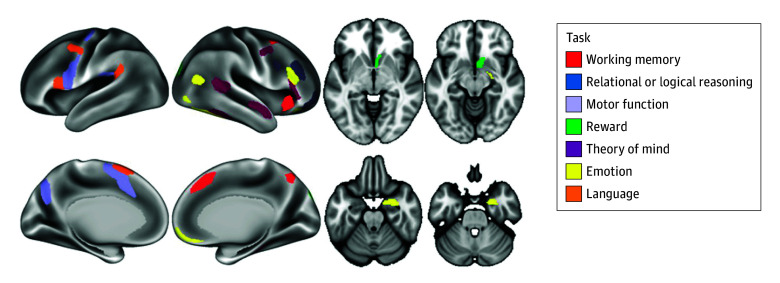

Seven tasks were used in this study, aiming to cover a broad range of behavioral processes.41 Tasks were chosen based on reliability of neural response and a well-characterized neurocognitive basis. The tasks examined neural response related to emotion, reward, motor function, working memory, language, relational or logical reasoning, and theory of mind or social information processing (task details are provided in the eMethods in Supplement 1). Neural response to the tasks has previously discriminated substance use history.42 For each task, we used the primary contrast, and we extracted activation levels from regions positively activated during the task (ie, regions engaged by the task, not regions that were deactivated by the task, such as nodes in the default mode network). Positive activation was defined as having significant activation (2-tailed P < .001), with most effect sizes (Cohen d) greater than 1.00 for the contrast (the task positive condition minus the control condition).43 We used the mean value of the activation levels across the listed regions for each task, so each participant had a single value representing the activation level for each task; the regions used are depicted in Figure 1. We chose to use a single value because (1) it reduced the number of outcomes for analysis, (2) it provided a more clinically interpretable metric, and (3) the activation levels across regions during a given task were not independent.44